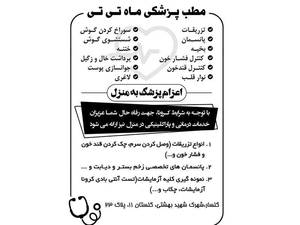

پزشکی، سلامت و زیبایی

پزشکی، سلامت و زیبایی